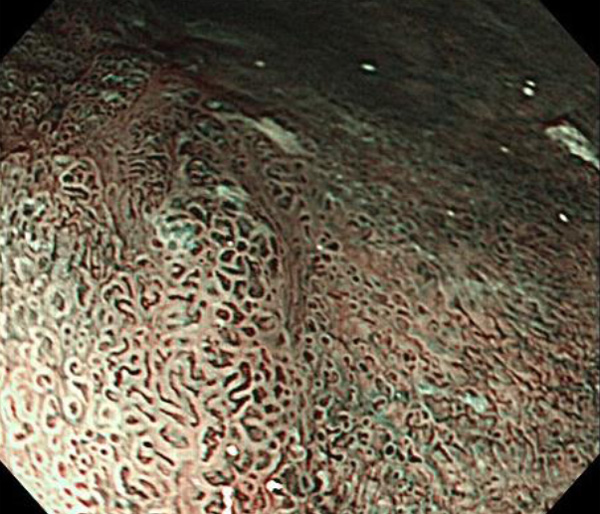

内視鏡所見と病理組織像の1対1対応が可能な症例を公募いたします。主にLSBEに発生した早期癌(HGDを含む)を対象としますが、興味深い症例であればSSBE癌でも結構です。採否は世話人へご一任ください。

症例呈示希望者は応募用紙に記入の上、代表的な内視鏡(2枚)、切除標本(新鮮、固定)、切り出し図、マッピング、代表的組織像とともに、Barrett 食道研究会事務局 barrett.shinshu@gmail.comへお申し込み下さい(10MB以下でお願い致します)。

特に、本邦では極めて稀なlong segment Barrett’s esophagus(LSBE)から発生した早期癌は、診断に難渋する場合も多く、欧米ではランダム生検による検出が標準的とされています。背景のBarrett食道もろとも全体を内視鏡切除+ラジオ波焼灼する欧米と異なり、ESDで内視鏡的な局所切除が基本の本邦では、存在診断+範囲診断(特に水平)を的確に行うことが不可欠です。

そのためには、一流の病理医による組織学的診断とエキスパート内視鏡医による拡大内視鏡像との一対一対応を徹底的に行うことで、『本来、見えないであろう拡大所見の先にある組織構築像が診えてくる』所まで内視鏡診断レベルを上げていく必要があります。その実現には、一対一対応を追究した症例(特にLSBE発生例)1例でも多く経験するしかありません。本研究会でBarrett食道腺癌(LSBE発生早期病変)を共に学び、拡大内視鏡像の一歩先を診るスキルを習得しましょう!一人でも多くの皆様のご参加をお待ちしています。

私は、Barrett食道癌はHGDも含め、内視鏡による存在診断、範囲診断が可能と信じて来ました。しかし最近、NBI拡大観察を併用しても側方範囲診断が不可能なLSBE症例を経験しました。診断技術を向上させるためには、多くの症例を診るしかありません。そこで、Barrett食道に造詣の深い先生方に世話人をお願いし、Barrett食道研究会を立ち上げることに致しました。全国からLSBE症例を集め、内視鏡的、組織学的診断に迫りたいと思います。皆様のご参加をお待ち致します。